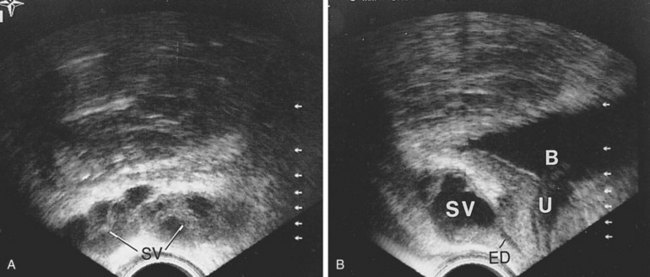

High-resolution transrectal ultrasonography (TRUS) has become the mainstay of imaging for the diagnostic evaluation of seminal vesicle pathology, because it is a reliable and inexpensive imaging modality. On TRUS, the seminal vesicles can be found just superior to the prostate, between the bladder and the rectum, and can be well visualized in the anteroposterior and sagittal views. The normal seminal vesicles should appear as flat, elongated, paired structures in the above described positions (Fig. 37–18). Along with the seminal vesicles, the ampullae of the vas deferens, the ejaculatory ducts within the prostate, and the verumontanum can be imaged and evaluated by TRUS. Abnormalities such as seminal vesicle obstruction, aplasia, atrophy, and cyst formation can be identified by TRUS (Carter et al, 1989).

Figure 37–18 Transrectal ultrasound examination of normal seminal vesicles. A, Transverse view. B, Sagittal view. B, bladder; ED, ejaculatory duct; SV, seminal vesicle; U, urethra.

Seminal vesicle obstruction may result in seminal vesicle dilation identifiable by TRUS with the following characteristics: anteroposterior diameter of greater than 15 mm, length greater than 35 mm, and large anechoic areas, which contain sperm when aspirated (Jarow, 1996; Colpi et al, 1997). Asymptomatic cystic dilation of the seminal vesicle was incidentally found in 5% of men undergoing TRUS for prostate cancer screening (Wessels et al, 1992).